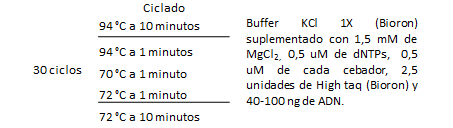

Se realizaron PCR con cada par de oligonucleótidos utilizando los genomas extraídos de la cepa silvestre. Los cebadores utilizados para la detección de las especies bacterianas A. actinomycetemcomitans, P. gingivalis, P. intermedia, T. forsythia y F. nucleatum fueron los que se muestran en la Tabla 1. Las condiciones de las PCR multiplex para la detección de estos microorganismos se muestran en las Tablas 2 y 3.

Tabla 3: Condiciones de la PCR multiplex para la detección de P. gingivalis, P. intermedia, A. actinomycetemcomitans